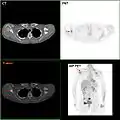

Tumor in the breast visualized by Breast-CT

Tumour in the breast visualized by Breast-Computertomography (Breast-CT)